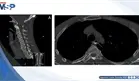

Perforación hipofaríngea simuló lesión menor: disfagia progresiva reveló ruptura de 2.5 cm